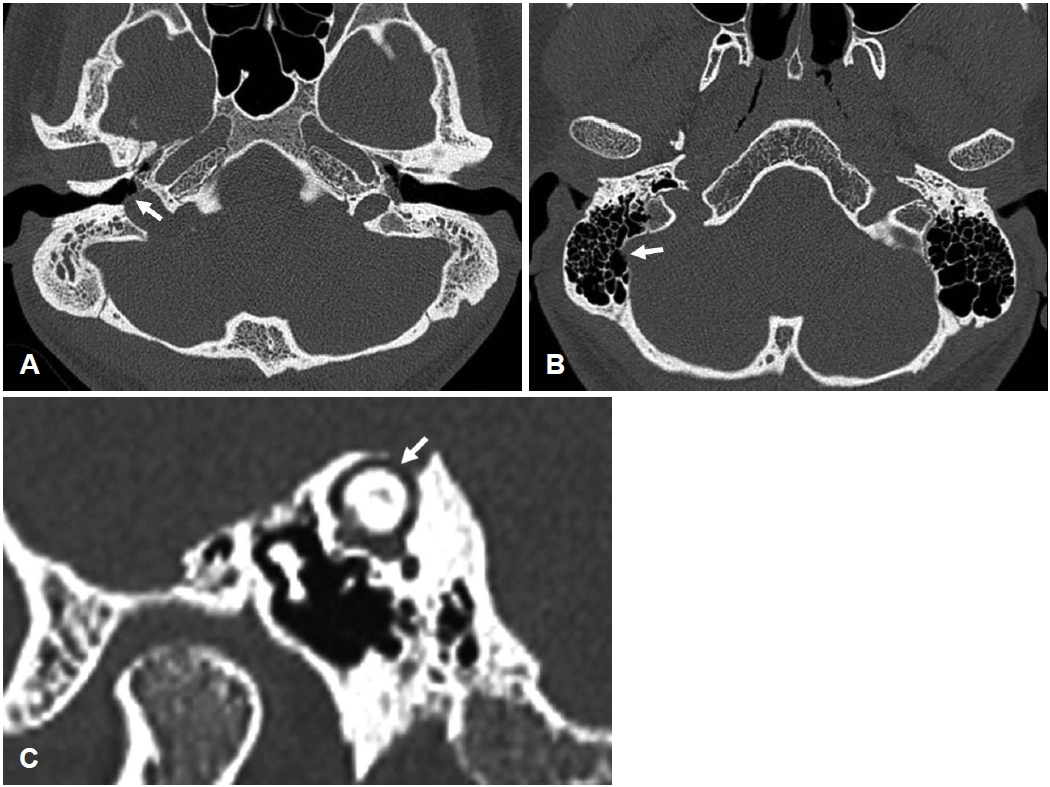

Carotid Artery-Cochlear Dehiscence Presenting With Pulsatile Tinnitus: A Case Report and Review of the Literature ( 440 times )

Ki Hun Jo, Jong Hyun Choi, Joo Yeon Kim, Jae Hwan Kwon

Received October 23, 2025     Accepted December 29, 2025     Published online February 10, 2026

DOI: https://doi.org/10.3342/kjorl-hns.2025.00521

[Epub ahead of print]

kjorl-hns-2025-00521f1.jpgkjorl-hns-2025-00521f2.jpg